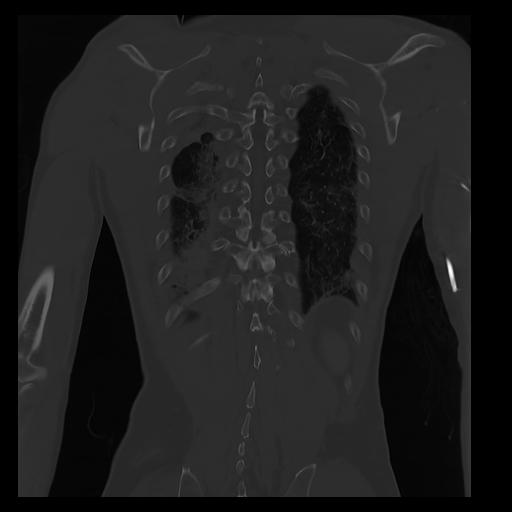

32 PULMON,CE,Coronal,3.000,PULMON,Coronal,